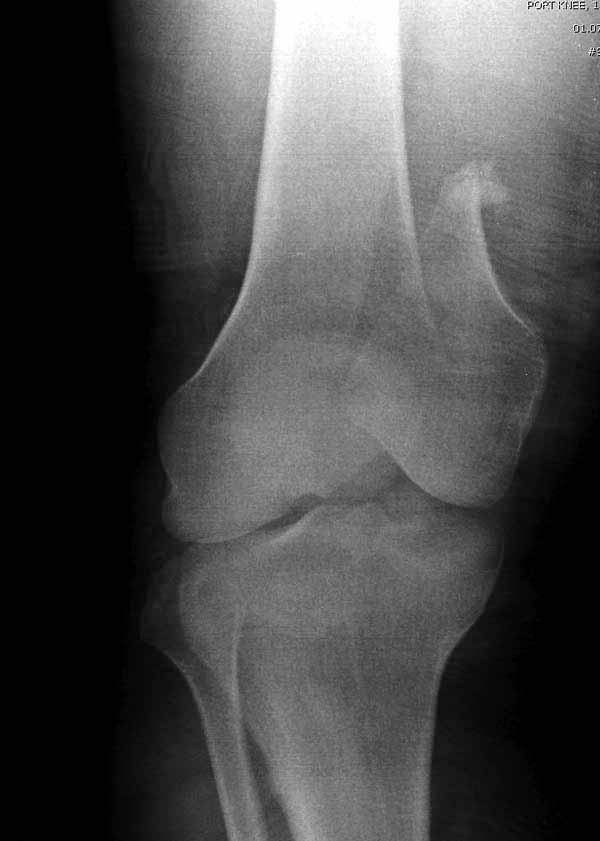

наружный мыщелок не дорепонироавн - это приводит к вальгусной деформации оси коленного сустава, очень критично для последующей функции.

Антеградное штифтование не очень годится при переломах типа C3, когда есть многооскольчатость именно суставной поверхности. А при переломах типа C1 и С2, т.е. и в обсуждаемом случае тоже, он как раз вполне оптимален. На межфрагментарную компрессию как-то не приходилось так драматически полагаться при интрамедуллярном остеосинтезе, результаты хорошие без нее были.

И уже лет шесть мы используем возможность ввести в дистальное овальное отверстие 3 винта, которые именно запираются в этом отверстии, не люфтят, а обеспечивают угловую стабильность - см картинку.

Получается и стабильно, и очень дистально, нижний край отверстия в 3 мм от дистального конца гвоздя.